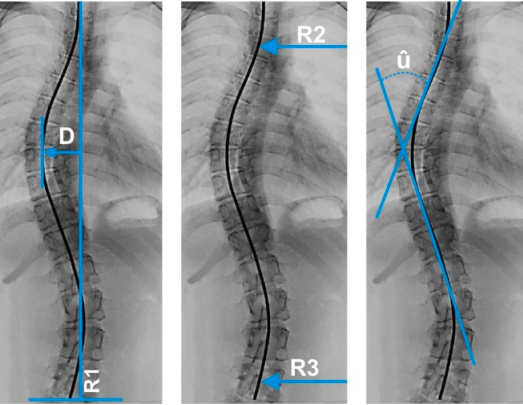

Quais são os métodos de avaliação radiológica da escoliose?

Os métodos de avaliação radiológica da escoliose incluem radiografias em pé e com inclinação lateral para medir a magnitude da curva.

Qual é o propósito do Método de Ferguson na escoliose?

O Método de Ferguson é utilizado para determinar o ângulo da curva escoliótica, auxiliando na avaliação da escoliose.